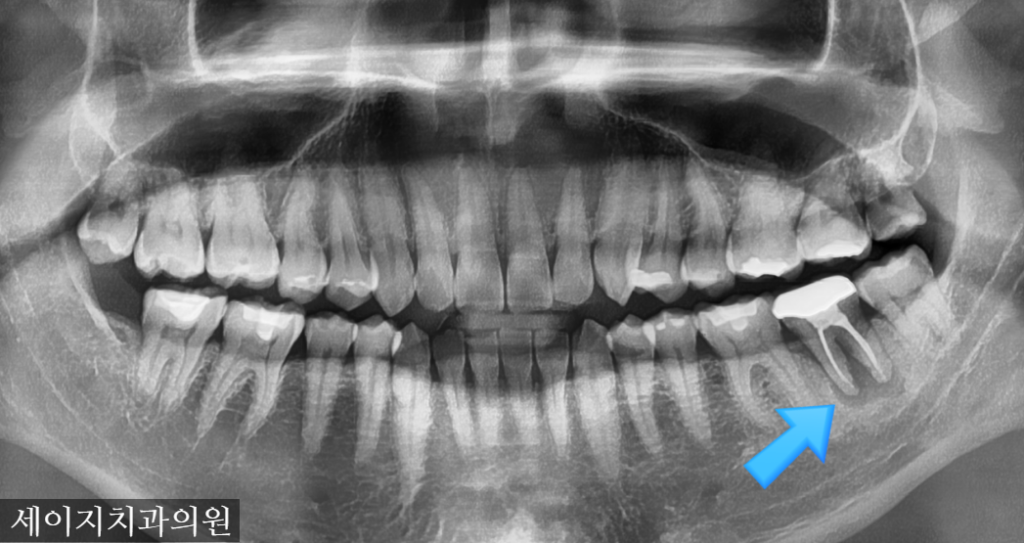

먼저 X-ray 장비를 이용하여 해당부위를 관찰하였습니다. 예상대로, 치아의 뿌리쪽에 염증이 생겨 있었으며 광범위한 상태의 골소실이 관찰되었습니다.

사진 설명을 입력하세요. 해당치아는 광범위한 골소실로 인해 발치로 치료계획을 설정하였습니다. 3D CT 장비를 이용하여 해당 부위의 골조직의 염증 부위를 확인하고 정확한 식립을 위해 모의 수술을 해보았습니다.

CT를 이용한 기존 모의 수술과 비슷한 결과값을 얻었으며 수술당시 광범위한 뼈이식을 통해 골조직을 재건해드렸습니다.